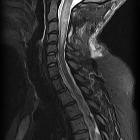

MRI

As astrocytomas arise from cord parenchyma (c.f. ependymomas that arise in the central canal), they typically have an eccentric location within the spinal cord.

They may be exophytic and even appear largely extramedullary. They usually have poorly defined margins. Peritumoral edema is present in ~40%. Intratumoral cysts are present in ~20% and peritumoral cysts are present in ~15%. Unlike ependymomas, hemorrhage is uncommon.

Reported signal characteristics include

- T1: isointense to hypointense

- T2: hyperintense

- T1 C+ (Gd)

- vast majority enhance (previously thought to be universally enhancing )

- usually patchy enhancement pattern